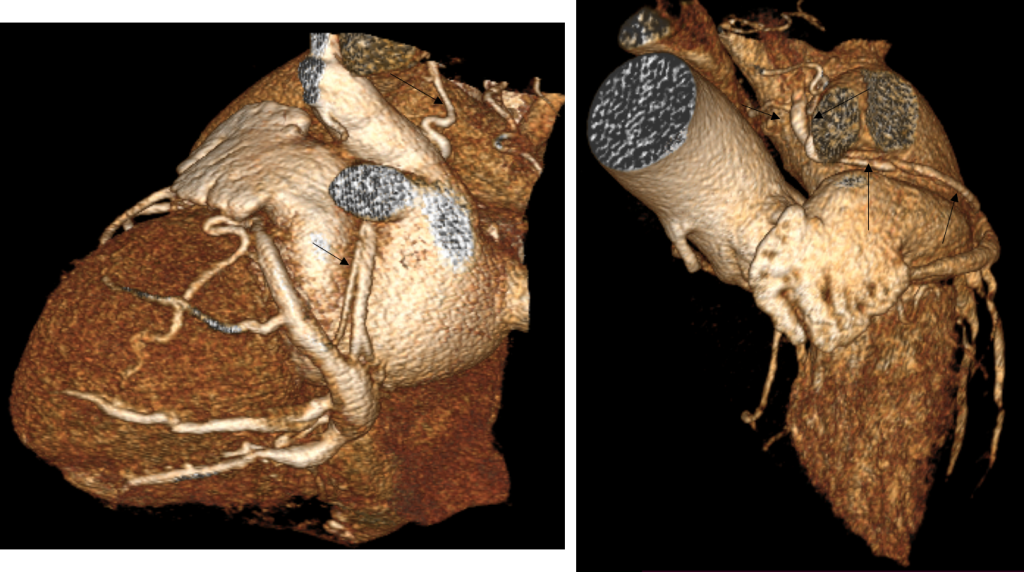

Fig 4 reconstrucţii volumice (VRT) din achiziţie angioCT coronariană

Discuţie caz nr 50: Examinarea angioCT coronariană este actual indicație de clasa 1 la pacienții cu boală coronariană cronică; este cazul unui pacient care a fost diagnosticat la examinare angioCT cu fistulă între arteră coronară dreaptă și arteră pulmonară dreaptă.